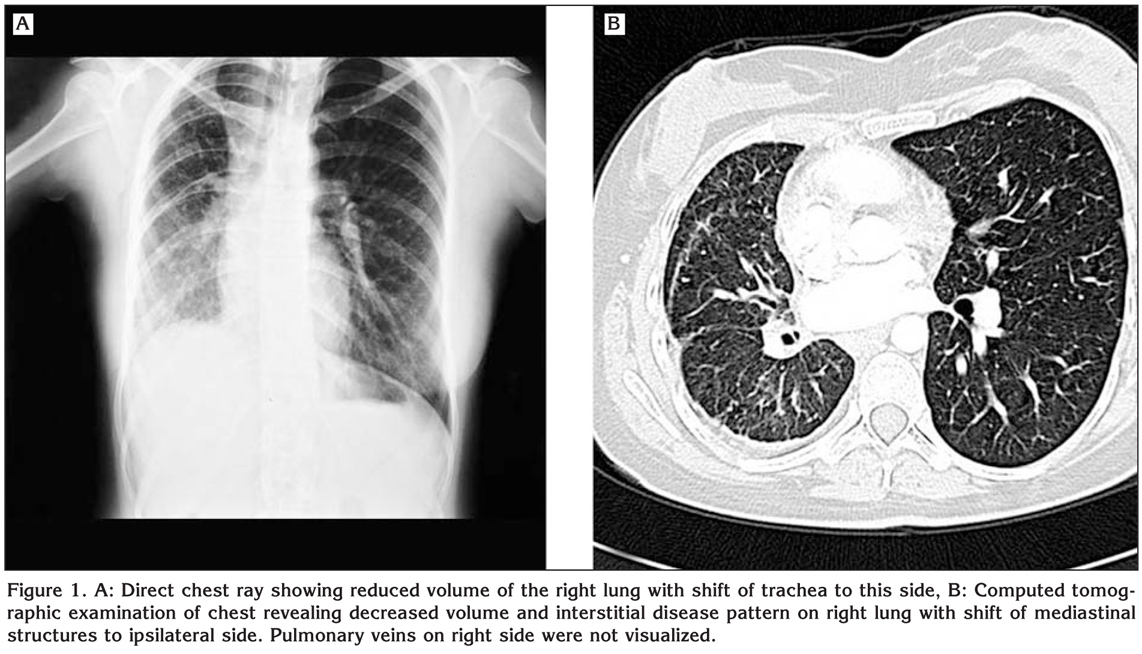

A 20-year-old female college student admitted to our clinic with dsypnea on exertion. She had this complaint for two years. On her past medical history she had pneumonia three years ago. On physical examination respiratory sounds were decreased on right hemithorax and cracles were heard on base of the right lung. Direct chest X-ray was obtained which revealed reduced volume of the right lung with shift of trachea to this side (Figure 1A). Computed tomographic examination of the chest showed decreased volume and interstitial disease pattern on right lung with shift of mediastinal structures to ipsilateral side. Right pulmonary veins were not identified on tomographic scans (Figure 1B). On transthoracic Doppler echocardiographic examination the right pulmonary veins were also could not be visualized. The estimated systolic pulmonary pressure on Doppler examination was normal. The right and left ventricular function were found as normal and interatrial and interventricular septums were intact. To confirm the diagnosis cardiac catheterization and pulmonary angiography were performed. On oxymetric study oxygen saturation was higher on right pulmonary artery than that of the left (99% vs. 89%, respectively). This finding suggested the presence of systemic arterial blood flow to pulmonary arteries on the affected side. On selected left pulmonary artery angiography the perfusion of the left lung was identified to be normal with normal pulmonary veins draining into left atrium (Figure 2A). However on selected right pulmonary angiography decreased perfusion of the right lung was noted and pulmonary veins on this side were not visualized (Figure 2B). Instead prominent intercostal arteries were identified supplying blood to the right lung. The patient was discussed with cardiologists and cardiovascular surgeons and conservative approach was chosen for her. She and her family were informed about this condition and close follow up were scheduled.

Figure 1